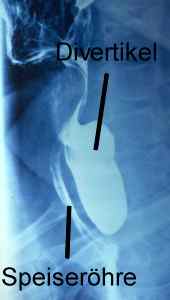

Röntgenbild eines Zenkerdivertikels. Die Speiseröhre und das Divertikel sind mit Röntgenkontrastmittel gefüllt.